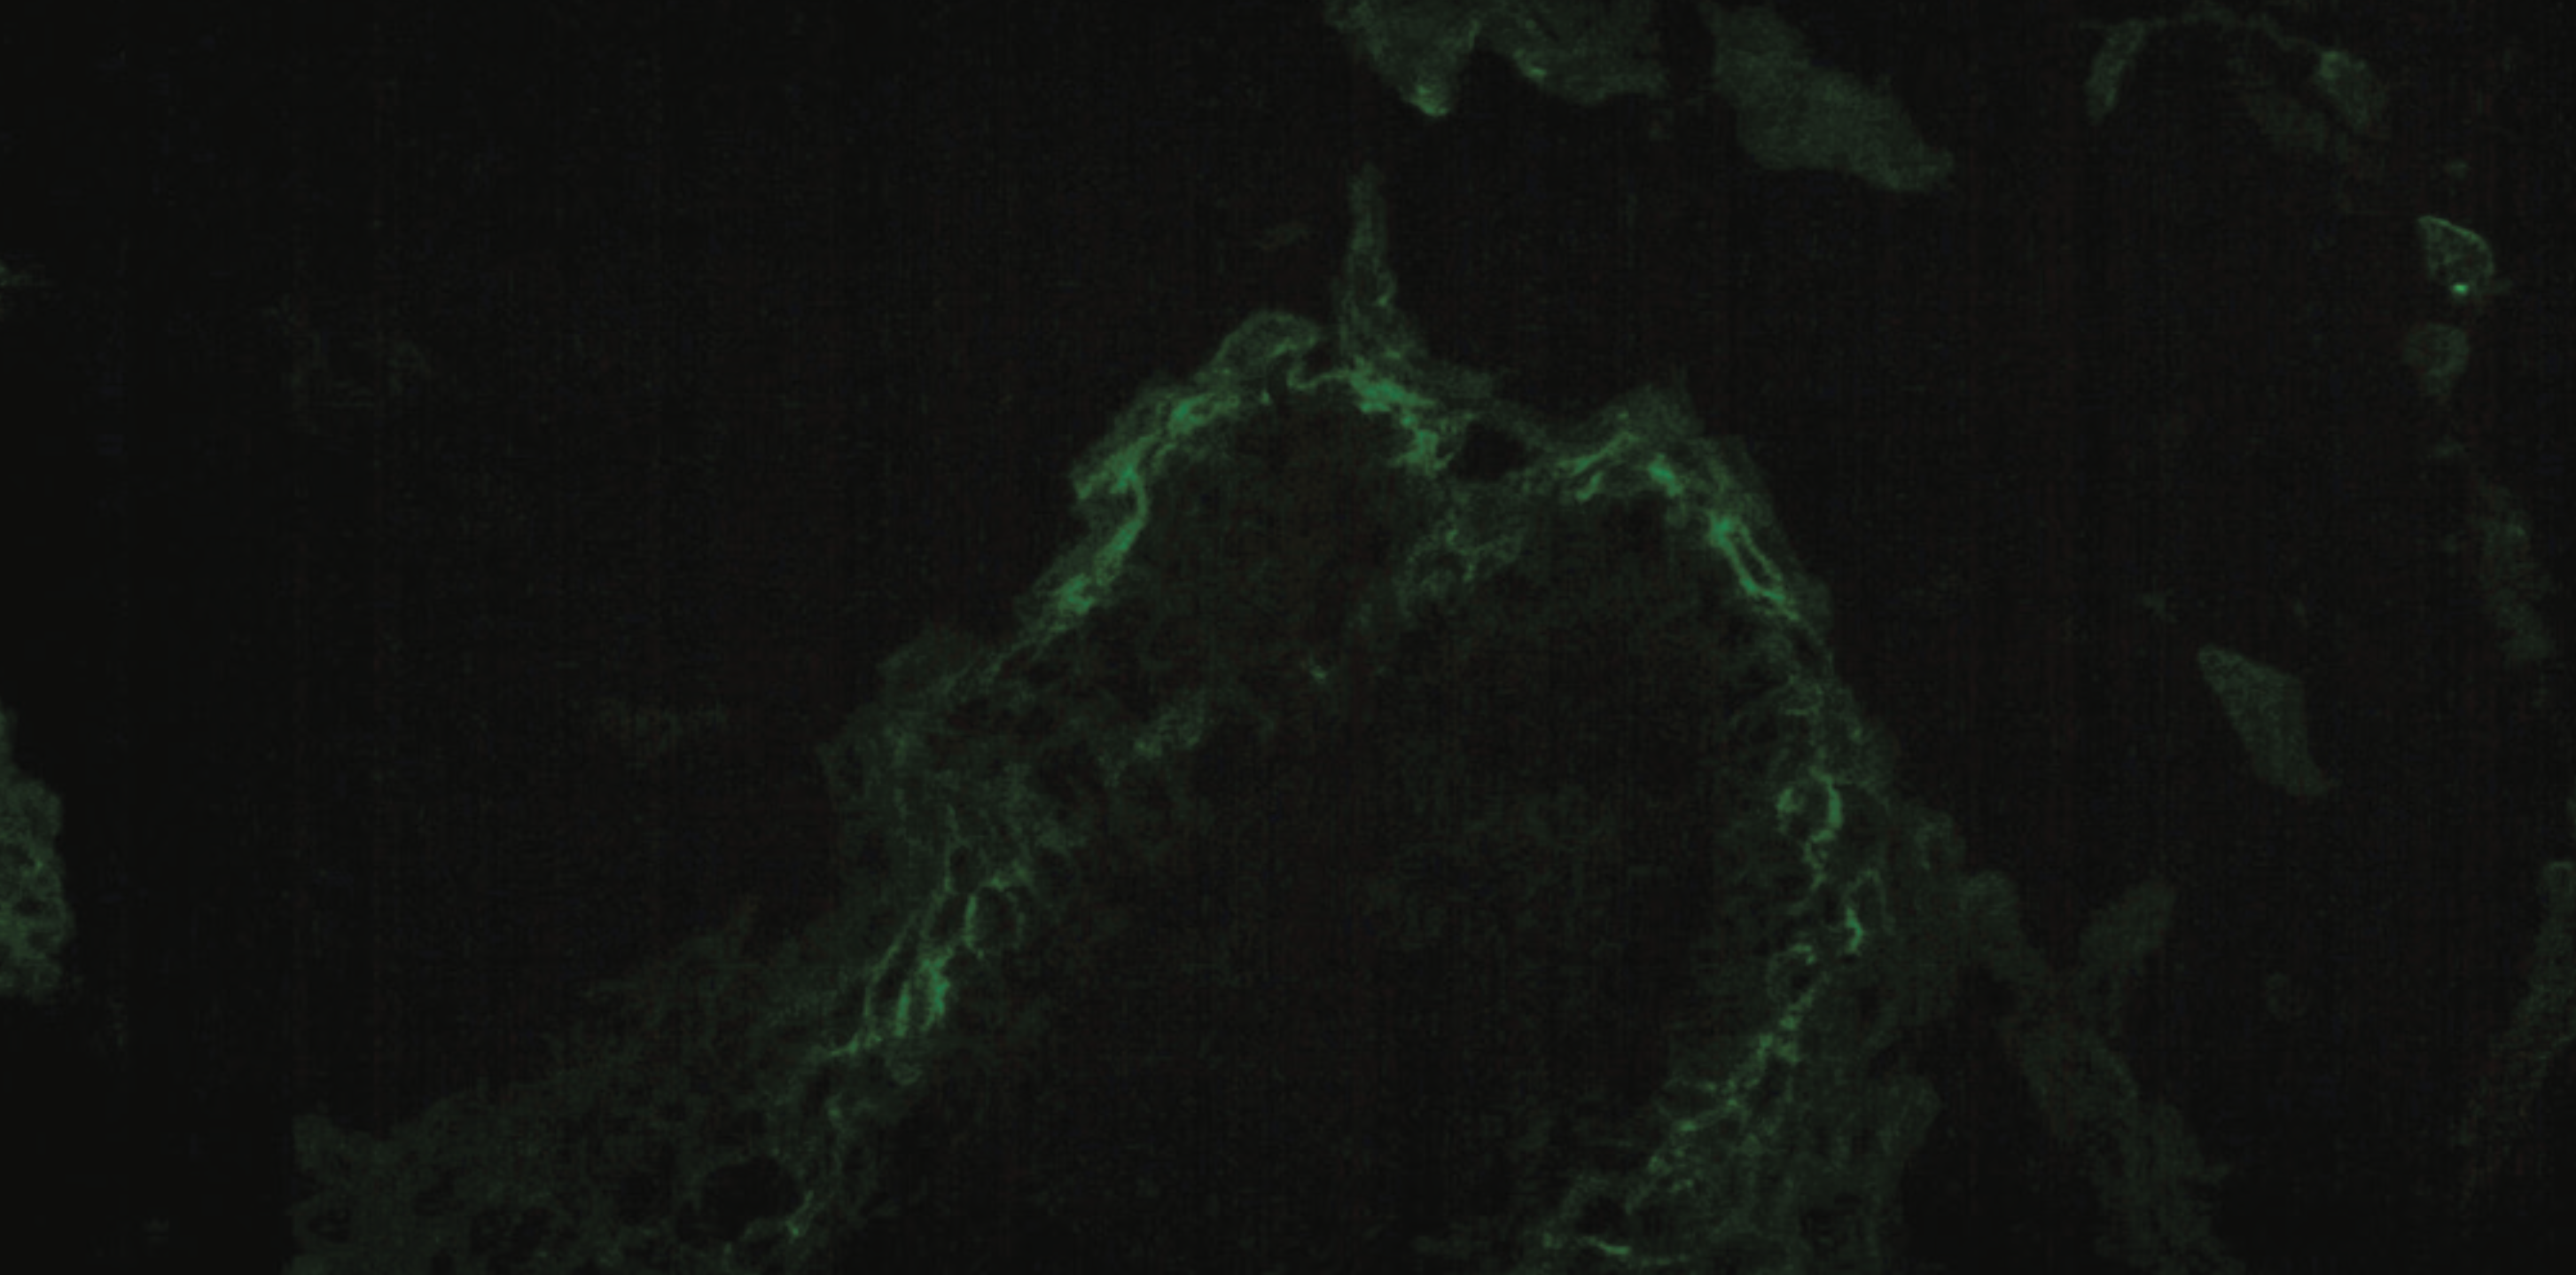

Punch biopsy hematoxylin and eosin (H&E) staining showed subcorneal/intraepidermal vesicular dermatitis with prominent acantholysis extending into the hair follicles and dermal perivascular lymphocytic infiltrate (Figure 2). Periodic acid-Schiff staining was negative for fungal hyphae. Direct immunofluorescence (DIF) demonstrated positive intraepidermal intercellular deposition of immunoglobulin G (IgG) and complement component 3 (C3) (Figure 3). These biopsy results suggested a diagnosis of PF. Subsequent serum studies using enzyme-linked immunosorbent assays (ELISA) were positive for desmoglein 1 (DSG1) antibody and negative for desmoglein 3 (DSG3) antibody, further supporting the diagnosis.

Although nonspecific, the histopathology of PF is characterized by subcorneal acantholysis,5 as seen in Figure 2A. Other findings may include intraepidermal blisters containing neutrophils and acantholytic keratinocytes,17 dermal inflammatory infiltrate,7 and follicular acantholysis,13 as seen in Figure 2B. Acanthosis, hyperkeratosis, parakeratosis, and granular layer dyskeratosis may be present in older PF lesions.7 DIF showing a “chicken-wire” distribution of interkeratinocyte deposition of IgG with or without C3 is diagnostic for pemphigus. In PF, deposition is predominantly in the superficial epidermis.5,6 Serum studies can also help determine the subtype of pemphigus. Indirect immunofluorescence, as with DIF, would reveal intercellular IgG deposition in the upper epidermis. ELISA in patients with PF is positive for antibodies to DSG1 but typically negative for antibodies to DSG3, a key distinguishing factor from pemphigus vulgaris (PV).5-7 ELISA titers may also be used to monitor disease activity.7